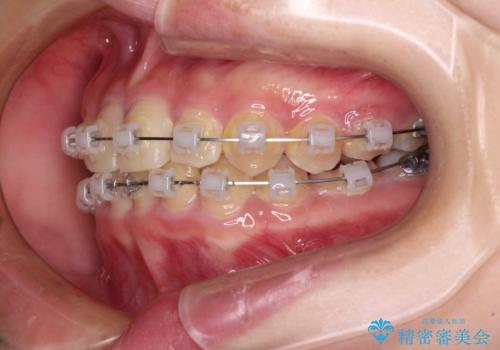

- クリアブラケット

- 犬歯のクロスバイトを気にして来院された患者様です。

マウスピース矯正とワイヤー矯正の両方を提案しましたが、インビザラインの自己管理が煩わしいとのことで、ワイヤー装置による矯正治療を行うこととしました。

犬歯は歯根が太くて長いため、クロスバイトを改善するのは大変であることが多いですが、比較的スムーズに改善することができました。

インビザラインであったら、もっと期間はかかっていたような印象です。